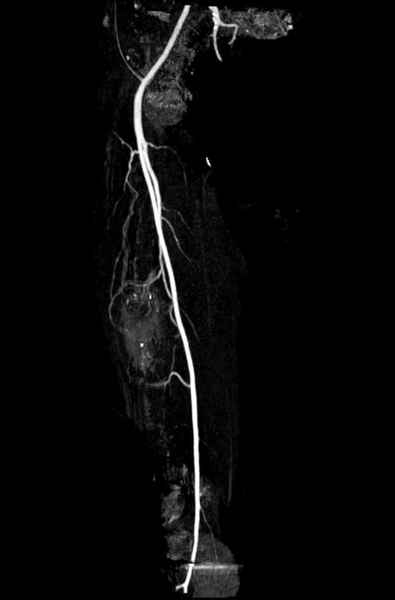

В зависимости от характера опухоли некоторые патологические переломы имеют риск кровотечения во время операции. Множественные литературные данные подтверждают, что надо проявить осторожность при интрамедуллярном остеосинтезе при неизвестных опухолях, особенно где имеется подозрение на Renal Cell Carcinoma. (RCC- hypernephroma) http://www.bonetumor.org/tumors/pages/page64.html

Со слов, больная ничем не болела, только последние 3 месяцев чувствовала боли в бедренной области. КТ брюшной полости подтвердил увеличенную правую почку. (5-6)

Для предупреждения кровотечения во время рассверливания, за день до операции провели эмболизацию сосудов питающий метастаз. http://radiology.rsnajnls.org/cgi/reprint/150/3/673.pdf (7-11, 12-15-16)

С минимальным рассверливанием и ретроградным методом провели остеосинтез бедра 12 мм гвоздем. (17-20)

Кровопотеря во время операции меньше 100 мл.